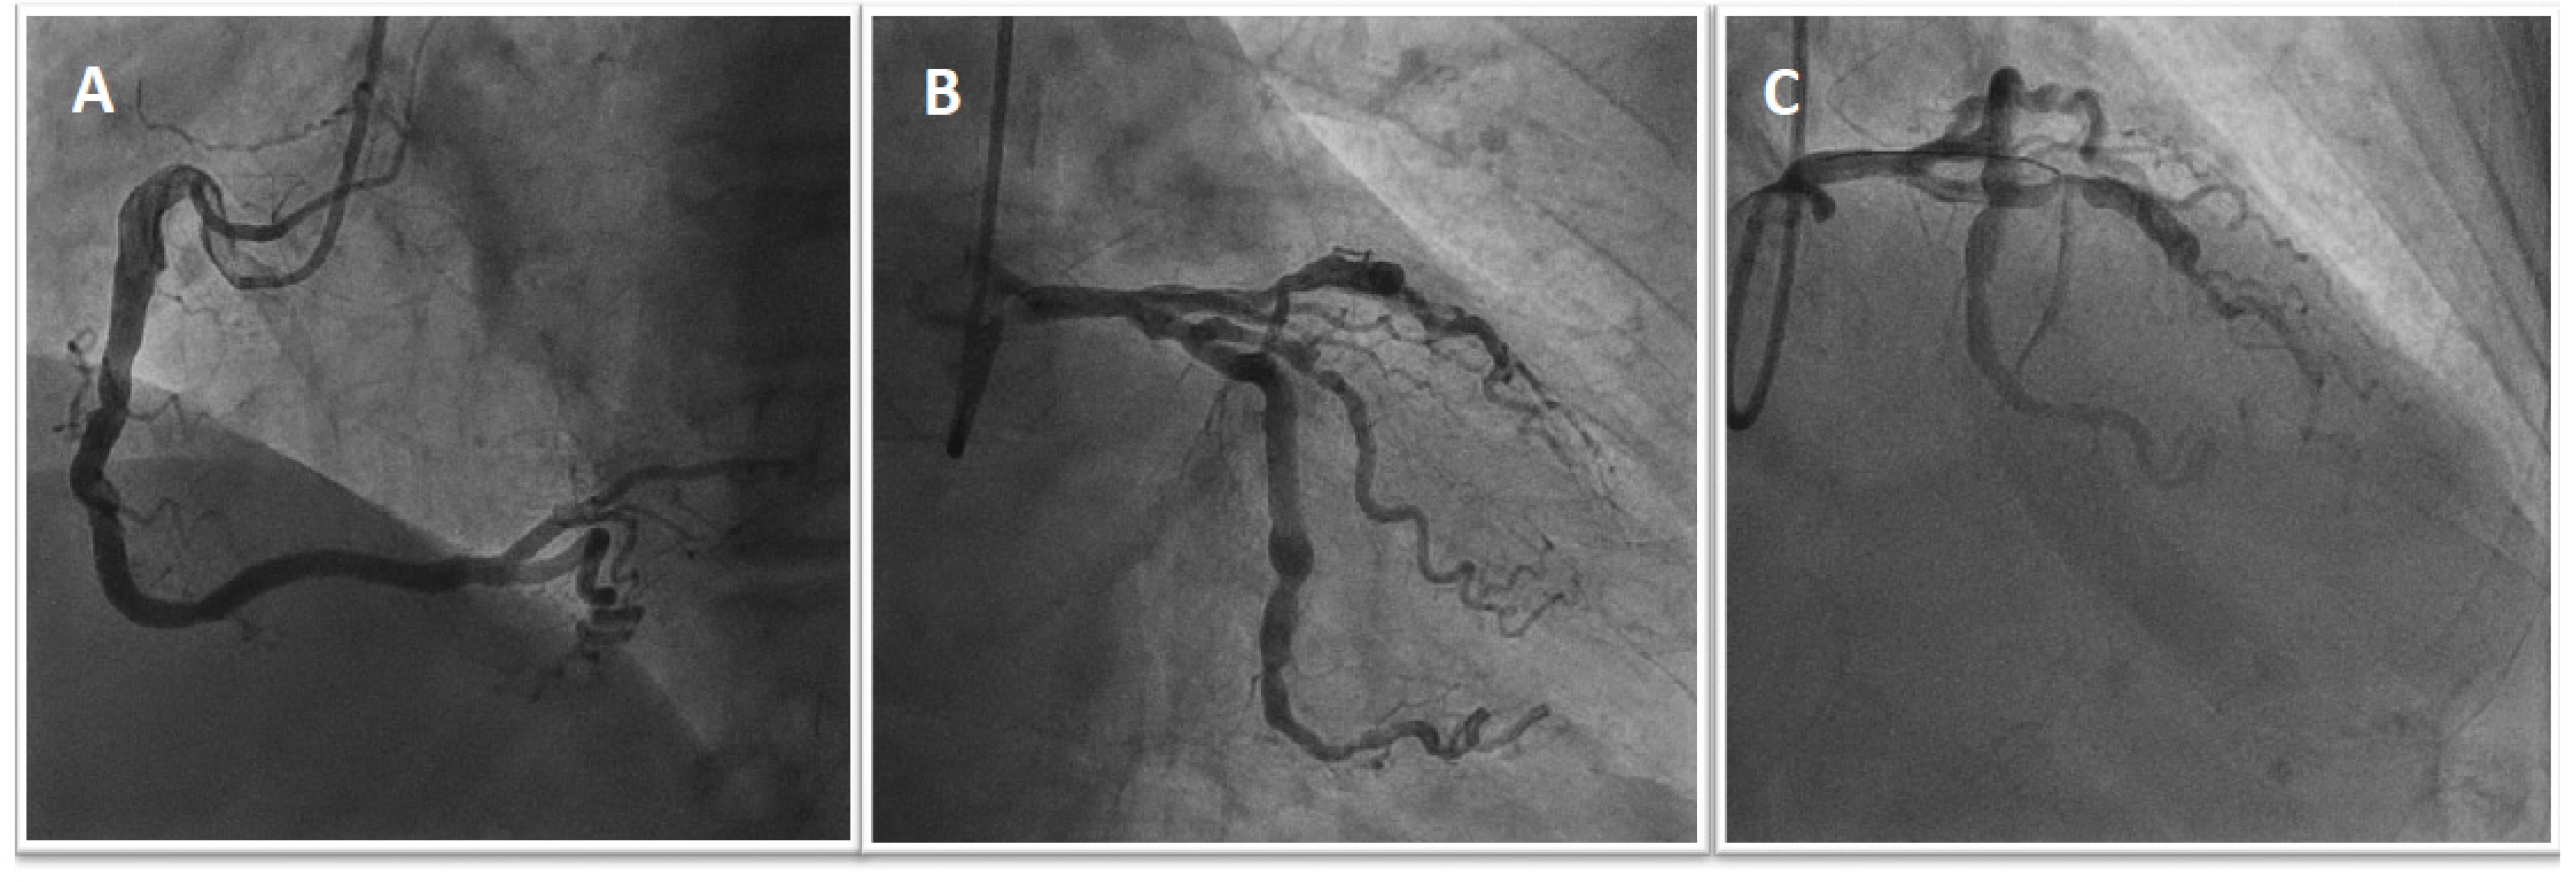

Figure 1.

Urgent coronary angiography shows atherosclerosis of the right coronary artery without significant stenosis (A), severe stenosis of the first proximal obtuse marginal artery (B), and acute occlusion of the mid-LAD with the presence of thrombus (C).